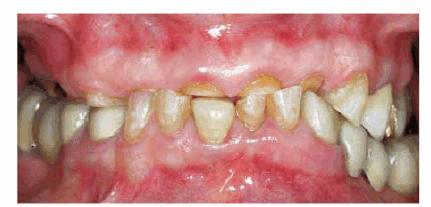

Figures 29-6A, 29-6B, 29-6C, 29-6D, and 29-6E illustrate a patient who did not care much about his

smile. The motivation for pursuing esthetic dentistry was his wife. She thought

that his smile made him look much older than his years. She encouraged him to

have esthetic dentistry by telling him that she would not kiss him until he had

his smile improved. Figures 29-6A, and 29-6D show the worn and discolored central incisors and the

crowded lower anterior incisors. Figure 29-6B shows cosmetic contouring of the lower incisors.

Figures 29-6C, and 29-6E illustrate the completed esthetic improvement following

composite resin bonding of the central incisors.

Figure 29-6A: This 65-year-old man displayed worn, discolored maxillary central incisors with a fractured anterior composite restoration on tooth #9.

Figure 29-6B: Cosmetic contouring of mandibular incisors.

Figure 29-6C: The view after composite resin bonding of his central maxillary incisors.

Figure 29-6D: This man avoided smiling to hide his worn, discolored, and fractured central incisors.

Figure 29-6E: Note how much younger and happier the patient is following his esthetic dental treatment.